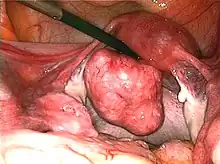

| Uterine fibroids as seen during laparoscopic surgery | |